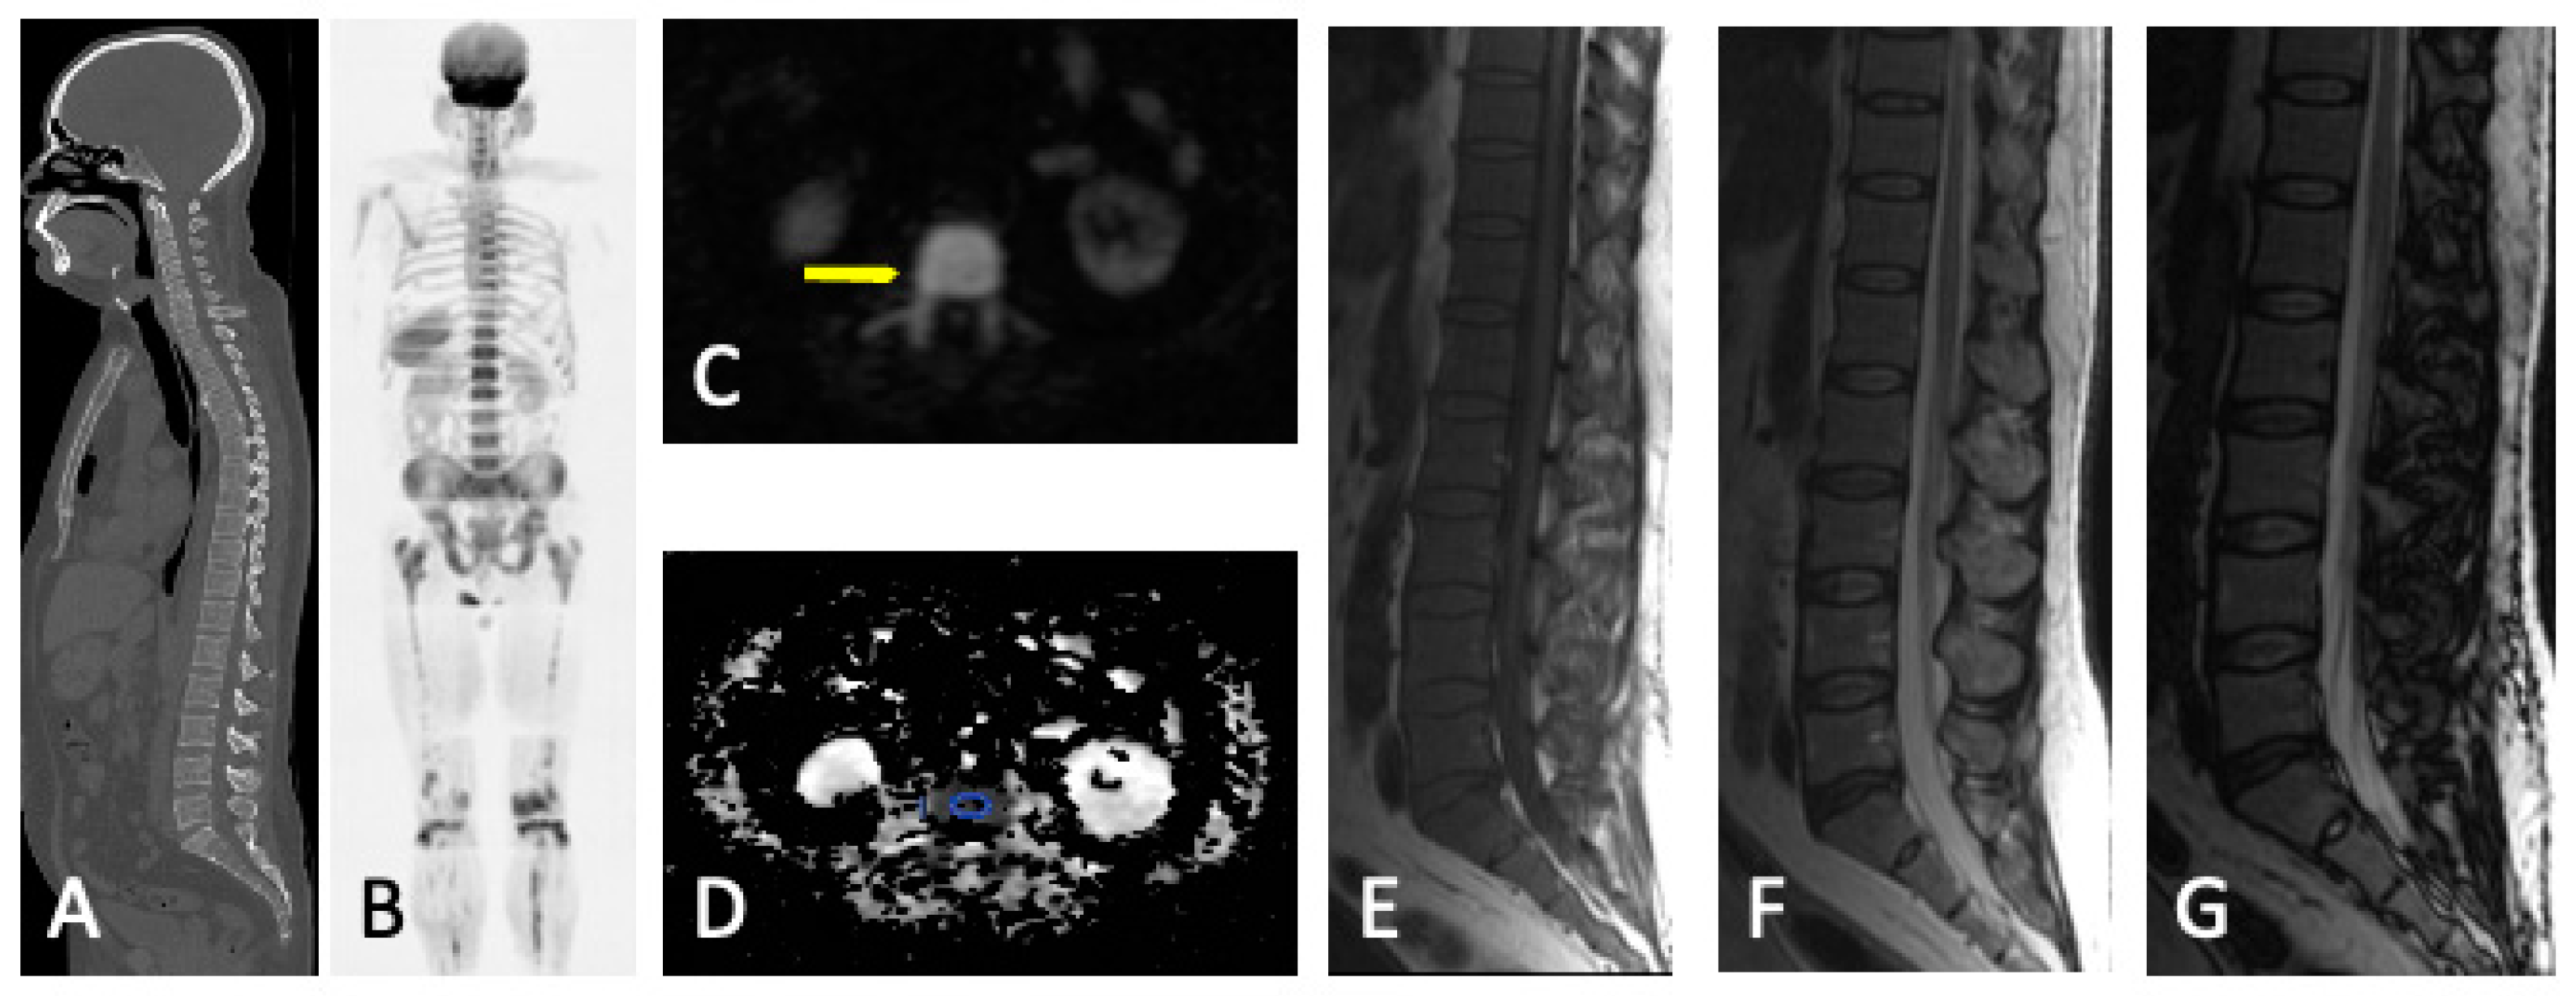

- Focal pattern: Focal myeloma infiltration was defined by circumscribed areas of high SI on STIR and T2WI. These corresponded to areas of low SI or, in a few cases, isointense signal upon an unenhanced T1WI [31]. The definition of focal lesion has evolved lately through the use of sequences such as DWI and Dixon. Therefore, focal lesions are defined as lesions greater than 5 mm hyperintense to background muscle at a b-value of 900 s/mm2, using ADC maps and confirming these findings with the corresponding Dixon sequences [32].

- Micronodular pattern: The micronodular or variegated or “salt and pepper” pattern presents a widespread heterogeneity with tiny nodular areas of altered diffusion signal (<5 mm) and T1WI hypointensities with preserved normal marrow between them [26].

- Diffuse pattern: Diffuse disease can be suspected from a diffuse decreased signal on T1WI (either iso- or hypointense to intervertebral discs and muscle) and a diffuse increased signal throughout the marrow on T2FSWI, STIR, or high b-value DWI. Marrow ADC values above 600–700 μm2/s in a nontreated and newly diagnosed patient with MM could be used to increase confidence for the diagnosis of diffuse marrow involvement [33] (Figure 7). Due to potential false-positive findings, diffuse disease in imaging must be supported by bone marrow trephine biopsy [26].

- Mixed pattern: This pattern combines diffuse and focal patterns.